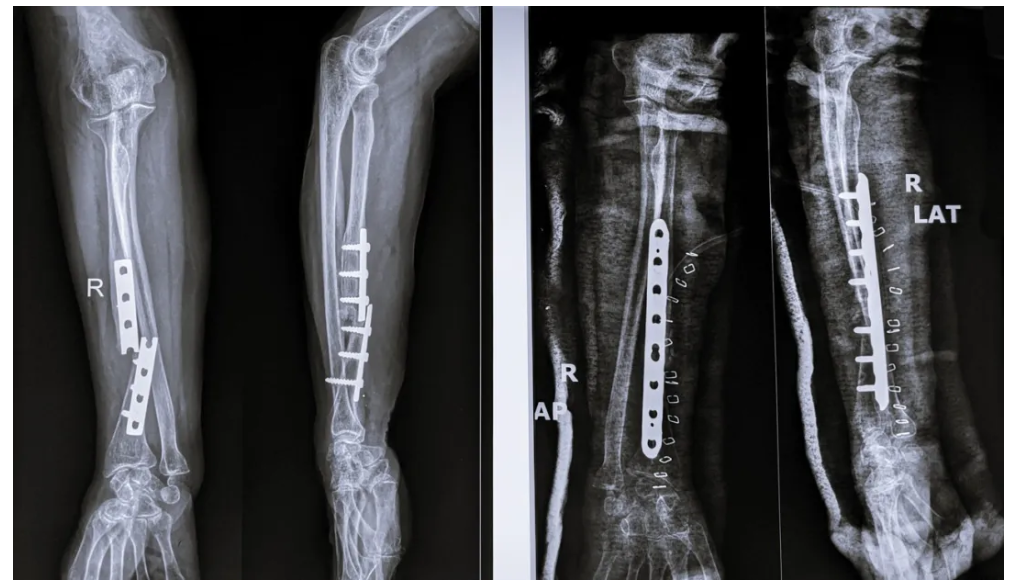

在传统手术疗法中,往往需要将骨块复位后,再使用钢板、螺钉等将其固定,听上去就令人头皮发麻。

打完钢板、螺钉后的骨头

图片来源:图虫创意

而且,有部分骨折并不是打完钢板钢钉就一劳永逸,还需要二次手术取出内固定物,这更是增加了患者的痛苦。如何提供更有效、微创的治疗方案,成为该领域最具挑战性的问题之一。

它在多家医院150余例受试病例中展现出了良好的安全性和有效性,各项指标达到预设标准。其中一位年轻工人因外伤致腕部粉碎性骨折,为避免传统的钢板内固定手术方案,医生通过一个2-3厘米的微创切口注入了“骨02”,便黏合了碎骨。术后复查显示,患者骨折愈合良好,手腕功能得以恢复。